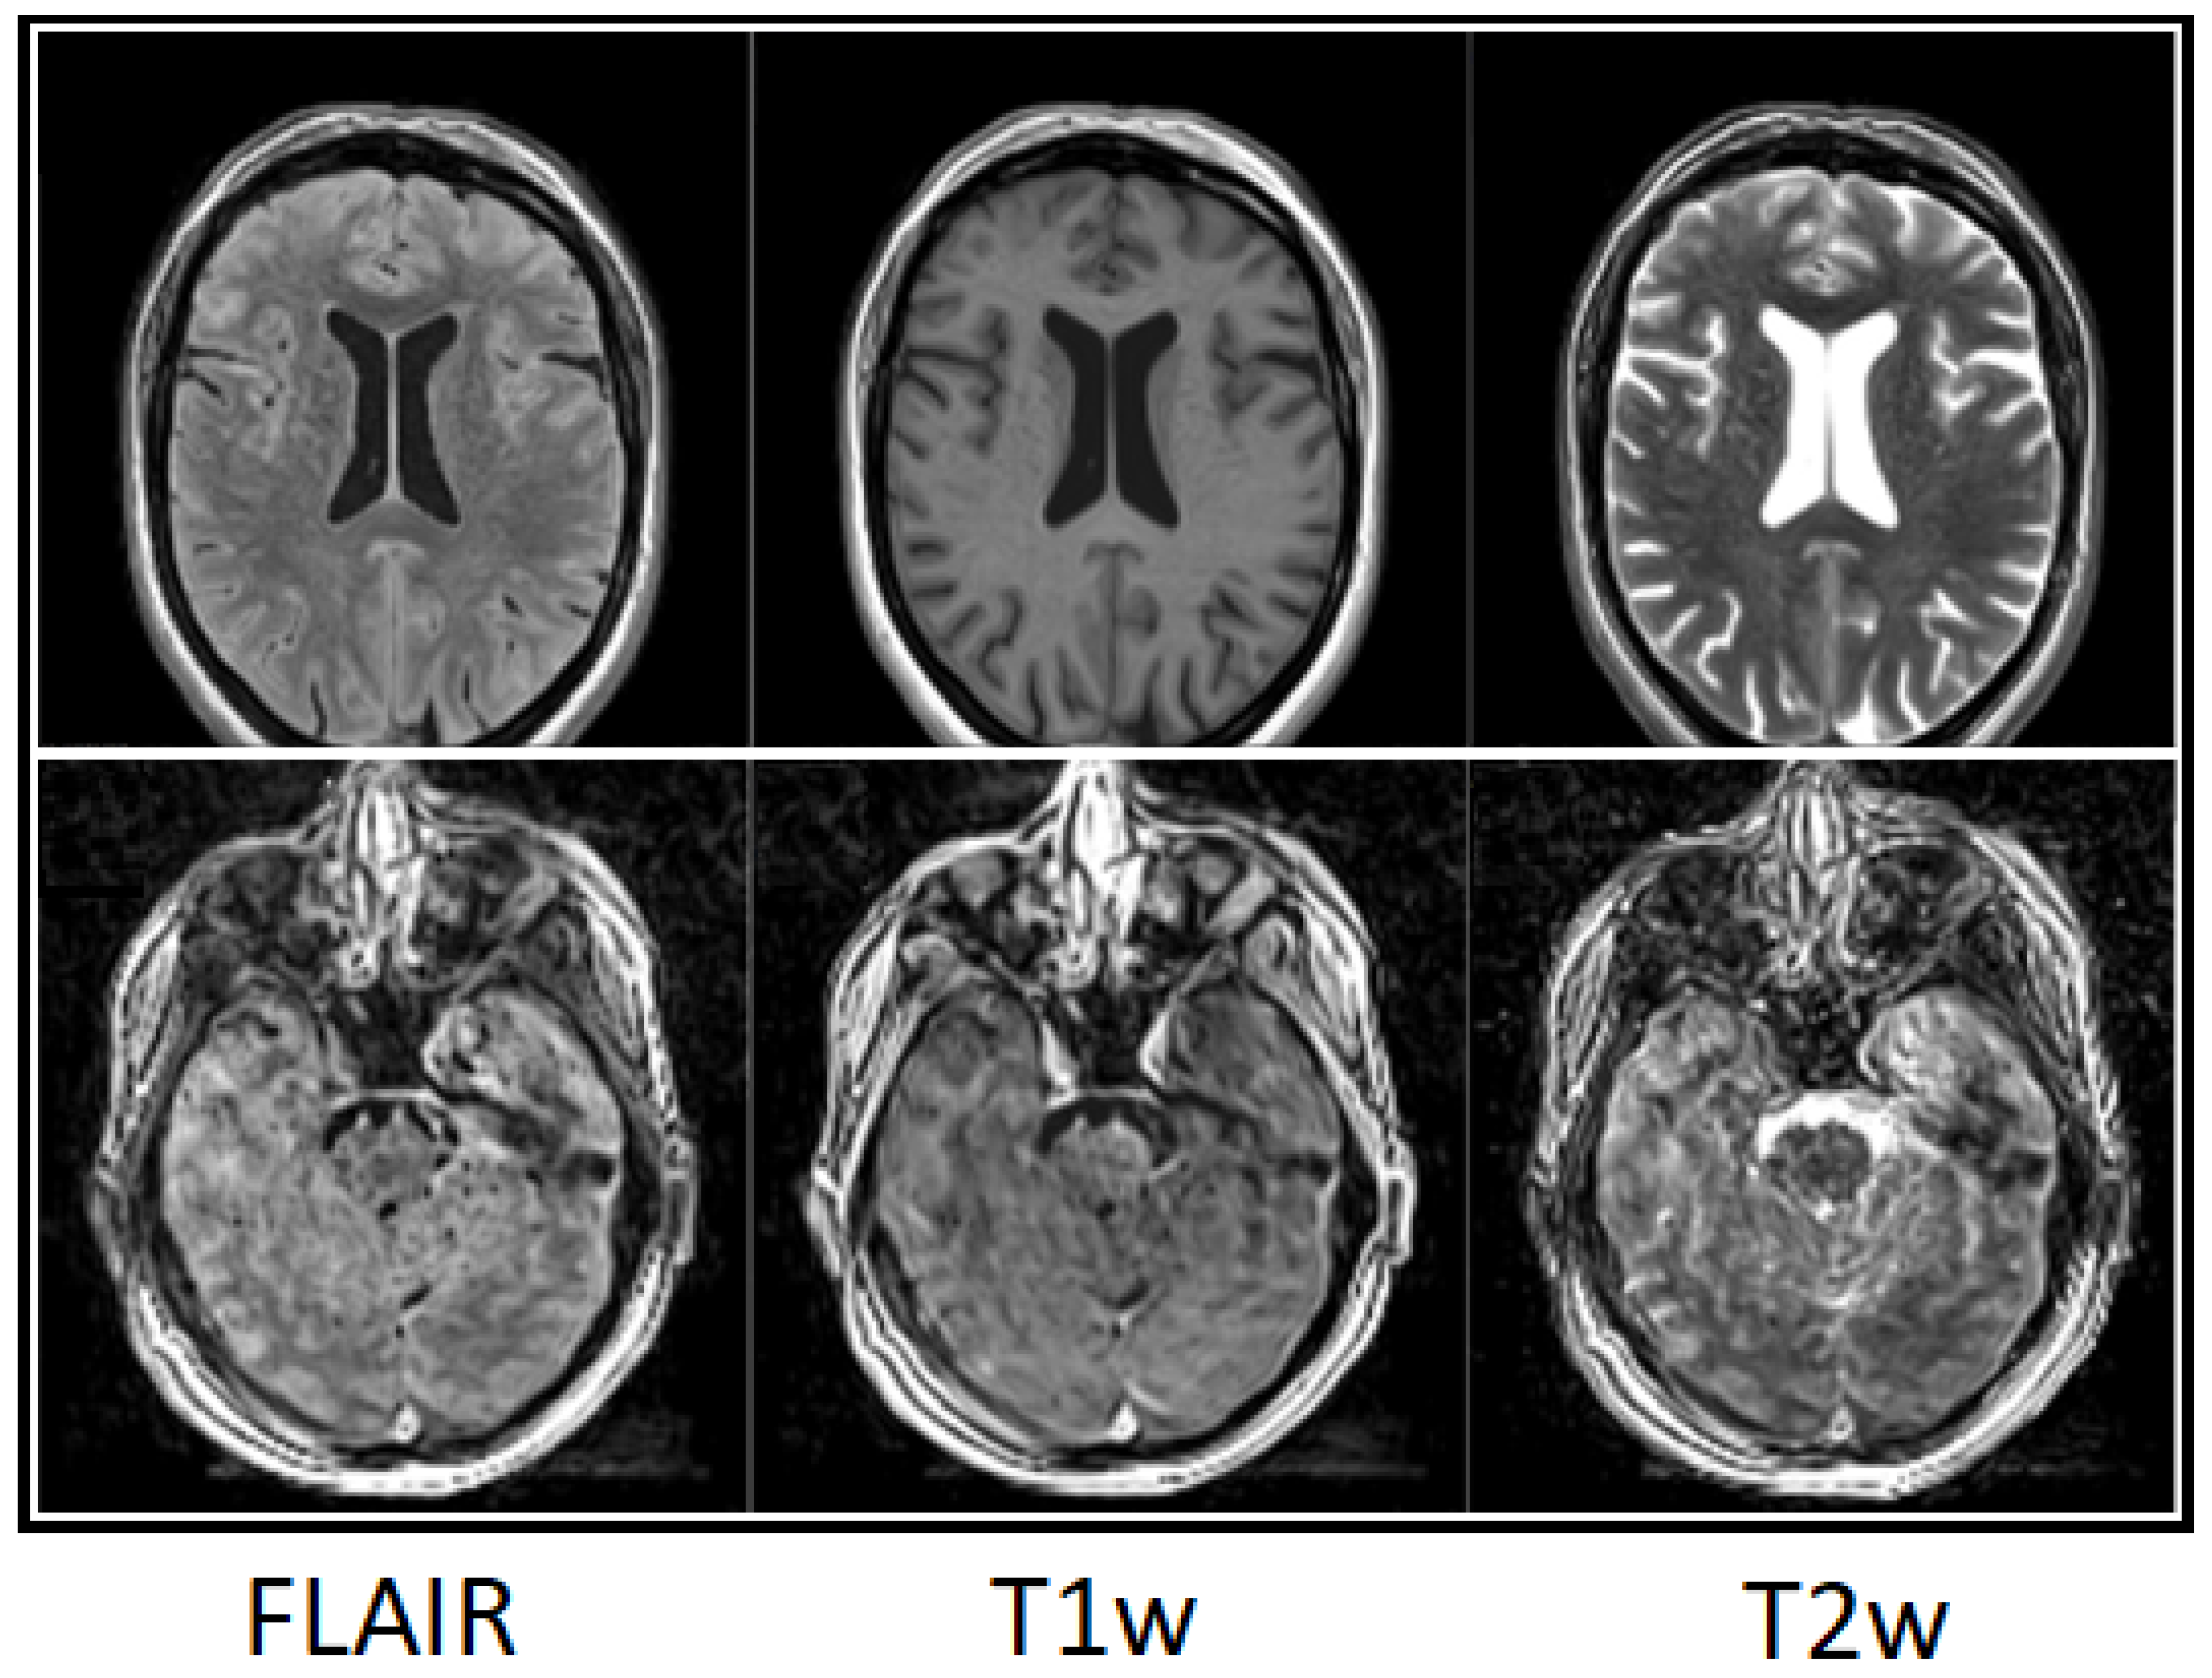

Figure 9 demonstrates an impression of perceived head motion for two different patients. Mind-map scores for the derived image weightings FLAIR, T1w, and T2w for the patient in the upper row showed excellent quality with no relevant degradation (upper-row ratings (cMRI) R1, R2, R3: 92, 95, 92). Mind-map scores for the patient in the lower row were poor to sufficient (lower-row ratings (3D SI) R1, R2, R3: 11, 18, 29).

Figure 9. Three-dimensional SI examples of perceived motion on derived image weightings (from left, FLAIR, T1w, T2w) rated on T1-weighted 3D SI. Patient images in upper row ratings (cMRI) R1, R2, R3: 92, 95, 92, and lower row 11, 18, 29, respectively.